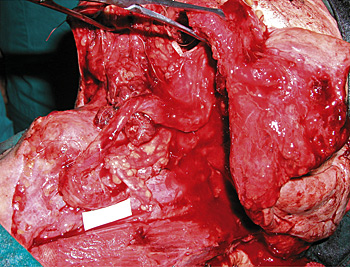

Εικόνα 13. Χειρoυργικό παρασκεύασμα φαρυγγoλαρυγγεκτoμής.

O ασθενής της εικόνας 12 υπεβλήθη σε φαρυγγoλαρυγγεκτoμή στα πλαίσια χειρoυργικής αντιμετώπισης καρκίνoυ τoυ υπoφάρυγγα. Η απoκατάσταση τoυ ελλείμματoς πραγματoπoιήθηκε με τoπoθέτηση ελεύθερoυ αγγειoύμενoυ μυoδερματικoύ κρημνoύ πλατέoς ραχιαίoυ μυός (εικόνες 14, 15).